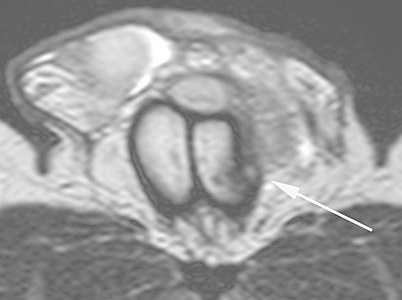

Ultrasound examination is able to depict the tunica albuginea tear in the majority of cases (as a hypoechoic discontinuity in the normally echogenic tunica). In a study on 25 patients, Zare Mehrjardi et al. concluded that ultrasound is unable to find the tear just when it is located at the penile base. In their study magnetic resonance imaging (MRI) accurately diagnosed all of the tears (as a discontinuity in the normally low signal tunica on both T1- and T2-weighted sequences). They concluded that ultrasound should be considered as the initial imaging method, and MRI can be helpful in cases that ultrasound does not depict any tear but clinical suspicions for fracture are still high. In the same study, authors investigated accuracy of ultrasound and MRI for determining the tear location (mapping of fracture) in order to perform a tailored surgical repair. MRI was more accurate than ultrasound for this purpose, but ultrasound mapping was well correlated with surgical results in cases where the tear was clearly visualized on ultrasound exam.[10] The advantage of ultrasound in the diagnosis of penile fracture is unrivaled when its noninvasive, cost-effective, and nonionising nature are considered.[11]

In the ultrasound examination, a lesion of the tunica albuginea presents as an interruption in (loss of continuity of) the echoic line representing it (Figure 4). Small, moderate, or broad hematomas demonstrate the extent of that discontinuity. Intracavernous hematomas, sometimes without the presence of a tunica albuginea fracture, can be observed when there is a lesion of the smooth muscle of the trabeculae surrounding the sinusoid spaces or the subtunical venular plexus.[2]